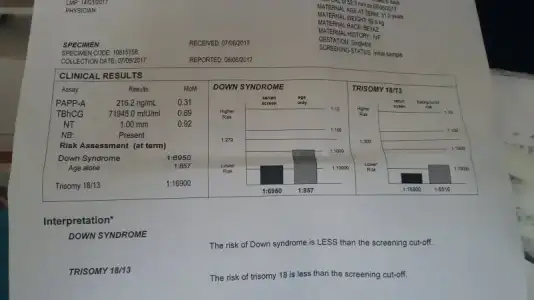

Doktrdan çıktım kızlar... doya doya izledim bebeği 15 dkk dan fazla maşlh ne güzl oynuyordu eli kolu  . Ense ölçümü iyi 1,35 ; 3 ten yukarı riskli imiş.. ikili ister misn dedi öneriyr musunz dedim sadece teklf ediyrz , ayrıca bu sadece bi olasılıkmış,, ben yine de yaptım..

. Ense ölçümü iyi 1,35 ; 3 ten yukarı riskli imiş.. ikili ister misn dedi öneriyr musunz dedim sadece teklf ediyrz , ayrıca bu sadece bi olasılıkmış,, ben yine de yaptım..

progestanı bırakıyrm folbiol bırakıyrm şu an sadece sulandırıcı.. haftaya test sonucu çıkarmış inşlh ii haberler alırız..

Kızlar bugün ikili tarama için gittim ense kalnlığı 0,178 çıktı burun kemiği oluşmış dedi ölçümlerin iyi olduğunu söyledi doktorum çok şükür inşallah tahlilde iyi çıkar. Cinsiyeti konusunda %60-80 civarı erkek dedi ama kesin konuşmadı yine de sizce nedir cinsiyeti bebeğimin??? baş kısmı sağda, ayak kısmı solda biraz tlefonda parlamış görüntü